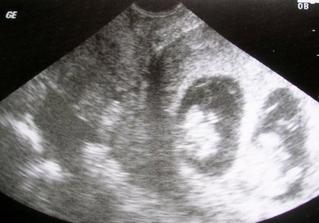

18.září jsme byli na našem 1.IVF... a 8.den od ET se mi "zjevily" nádherné // 🙂... přeju si,aby se všechno vyvíjelo dobře... 29.9 11.den po ET mi pro zhoršení OHSS provedli punkci Douglasova prostoru a odsáli 2 litry žlutého ascitu ☹ Nicméně se mi ulevilo 🙂 HCG ten den 259... 6.10 kontrola HCG - 2950 (18.den od ET)... 10.10 UTZ - čekáme DVOJČÁTKA 🙂 🙂 🙂... 17.10 krvácení a následná hospitalizace, UTZ - dvojčátkům bijí srdíčka, 20.10 HCG - 56000, 25.10 propuštění z nemocnice... 31.10 poslední kontrola v CARu, dvojčátka mají 2 a 2,1 cm... 11.11 UTZ - dvojčátka mají 3 cm... 24.11 UTZ - dvojčátka mají 9 cm (ale moc se mi to měření nezdá, ve čtvrtek na screeningu se ukáže pravda, čeká nás 3D 🙂) 27.11 screening I.trimestru - miminka jsou zdravá, od hlavičky po prdelku mají 7 cm... 19.12 3D - miminko "A" je chlapeček, "béčko" chce zůstat zatím v utajení 🙂 tak snad příště 🙂... 8.1 3D - miminko "B" je holčička 🙂 19.1 echokardiografie - obě srdíčka jsou zdravá 🙂 20.1 screening II.trimestru - vše OK, miminka mají 360 a 364 gramů 🙂 26.1 UTZ - chlapečkovi se ztratil pindík a najednou čekáme 2 holčičky 🙂) Doufám, že už je to definitivní 🙂) 19.2 UTZ 3D4 - holčičky potvrzeny!!! 🙂 mají každá téměř 800 gramů! 🙂 20.3 UTZ - holčičky mají 1700 a 1800 gramů! 8.4 UTZ - holky mají neuvěřitelné váhy 2415 a 2600 gramů! 11.5 nástup do nemocnice... 11.května ve 20,03 se nám akutním císařským řezem narodila Eliška (2970/48) a o minutu později Nelinka (3200/50).Jsme nejšťastnější rodiče na světě! 🙂